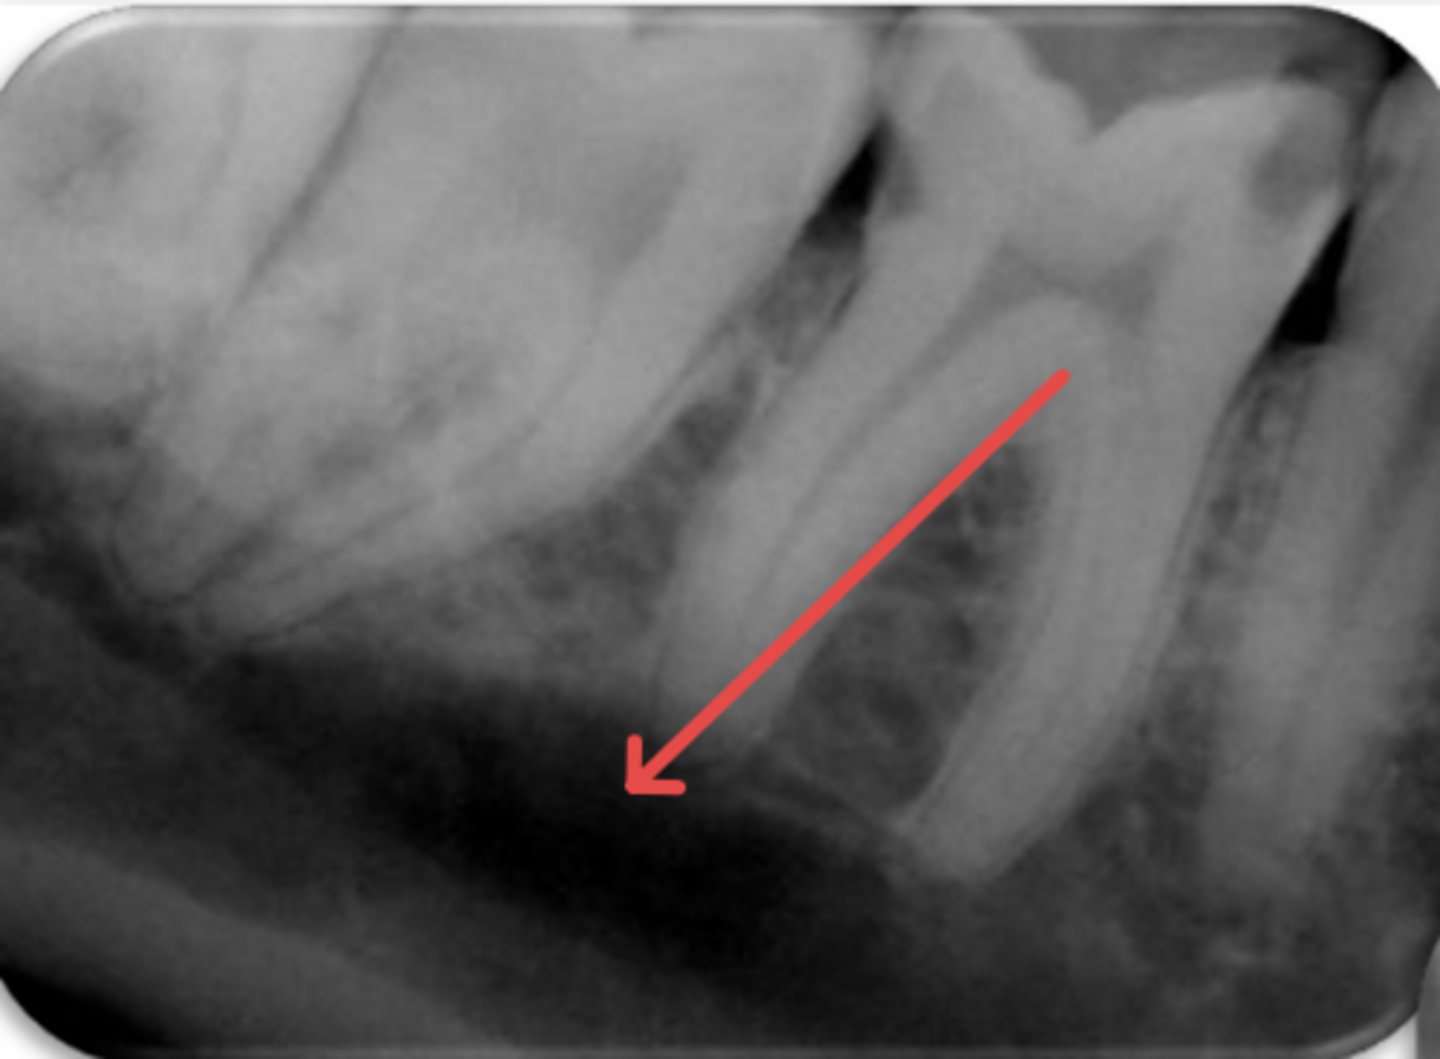

ID the problem:

fracture

vertical root fracture

- May not show on PA radiographs

Presents with signs of:

- J-shaped lesion/lateral radiolucency

- Isolated deep pocket

- Coronally located swelling or sinus tract